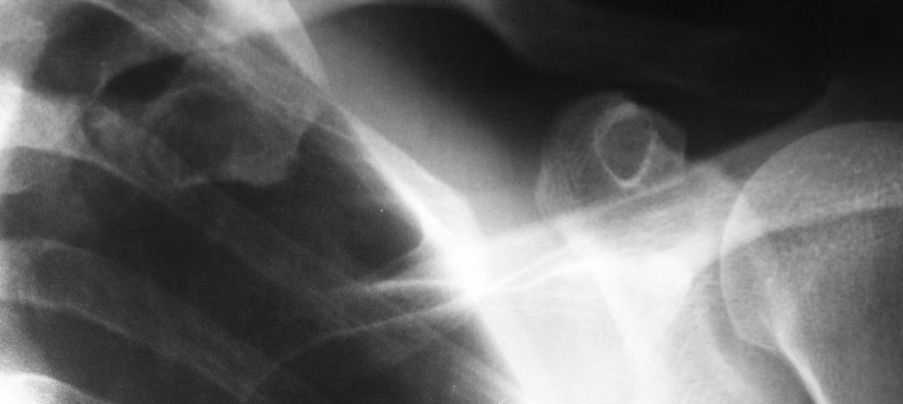

Костная киста первого ребра?

Уважаемые коллеги!Помогите определится с диагнозом и дальнейшей тактикой ведения больного

Пациент 42г,больным себя считает около месяца,когда появились боли при пальпации в области левой подключичной ямки,также беспокоят боли в области правого плечевого и ключино-акромиального сочленений.

Об-но:пастозность в левой подключичной области,боли при пальпации там же,кожные покровы физиологической окраски.При осмотре плечевого сустава -клиника плечелопаточного периартрита.

Приношу извинения за качество рентгенограммы